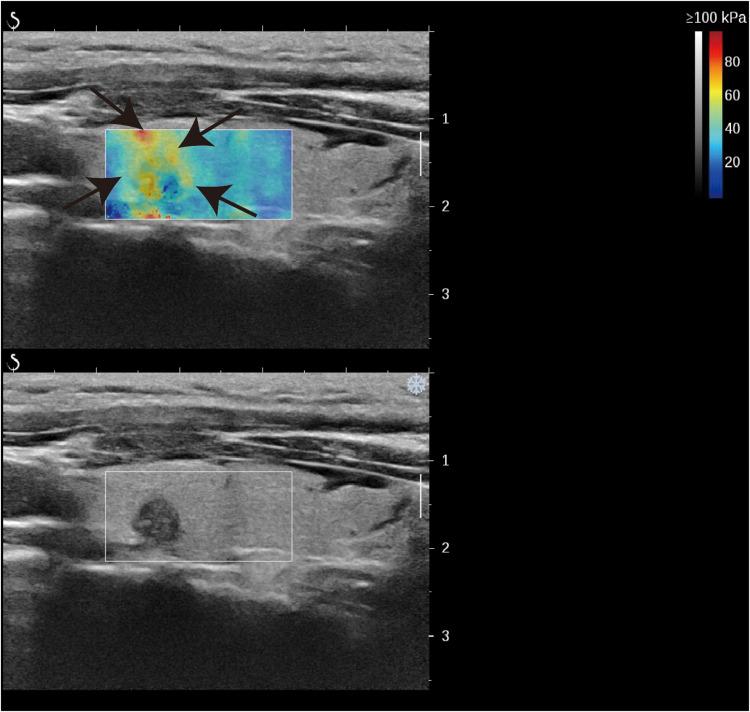

Ninety five thyroid nodules (48 benign and 47 malignant) from 81 patients were examined using Kwak Thyroid Imaging Reporting and Data System (TI-RADS) were subjected to shear wave elasticity (SWE), BRAFV600E genotyping and fine needle aspiration (FNA) cytology.

The modified TI-RADS exhibited superior diagnostic accuracy compared to TI-RADS in differentiating benign nodules from malignant thyroid nodules. Moreover, the AUC of modified TI-RADS in conjunction with BRAFV600E was the highest at 95% CI (0.898-0.992, p=0.003), surpassing other diagnostic methods in enhanced sensitivity and maintaining high specificity.

对81例患者的95个甲状腺结节(48个良性和47个恶性)采用Kwak甲状腺影像报告和数据系统(TI-RADS)进行检查,并进行剪切波弹性成像(SWE)、BRAFV600E基因分型和细针穿刺(FNA)细胞学检查。

在区分良性结节与恶性甲状腺结节方面,改良的TI-RADS比TI-RADS表现出更高的诊断准确性。此外,改良的TI-RADS联合BRAFV600E的曲线下面积(AUC)在95%置信区间最高,为(0.898 - 0.992,p = 0.003),在提高敏感性和保持高特异性方面超过了其他诊断方法。